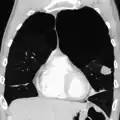

Section of a lung showing centrilobular emphysema, with enlarged airspaces in the centre of a lobule usually caused by smoking and a major feature of COPD